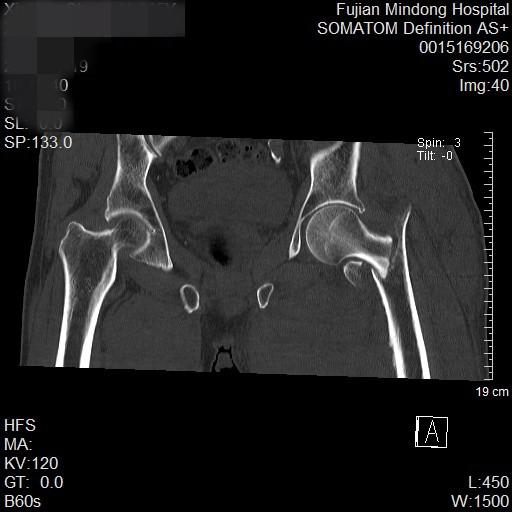

东南网12月1日讯(通讯员 程宏振)随着社会老龄化进程加速,高龄人群髋部骨折发生率显著上升,一次不经意地摔倒都可能造成严重威胁。其中,股骨粗隆间骨折作为骨科常见老年性疾病,其治疗方式经历了从保守治疗、传统大开刀手术到现代微创技术的革新跨越。

术前

近日,霞浦县一位85岁高龄的谢大爷,因摔伤导致左髋部剧痛、无法活动,于伤后第二天前往宁德市闽东医院就诊,被确诊为“左侧股骨粗隆间骨折”。创伤骨科何晓宇主任医师与张中宁副主任医师团队,为其实施了“左侧股骨粗隆间骨折闭合复位PFNA内固定术”。整台手术耗时约一小时,术中出血量仅约20毫升,展现了微创手术的优势。令人欣喜的是,术后第一天患者便能自行坐起,第二天即可站立,第三天已在助行器辅助下开始行走,恢复迅速。